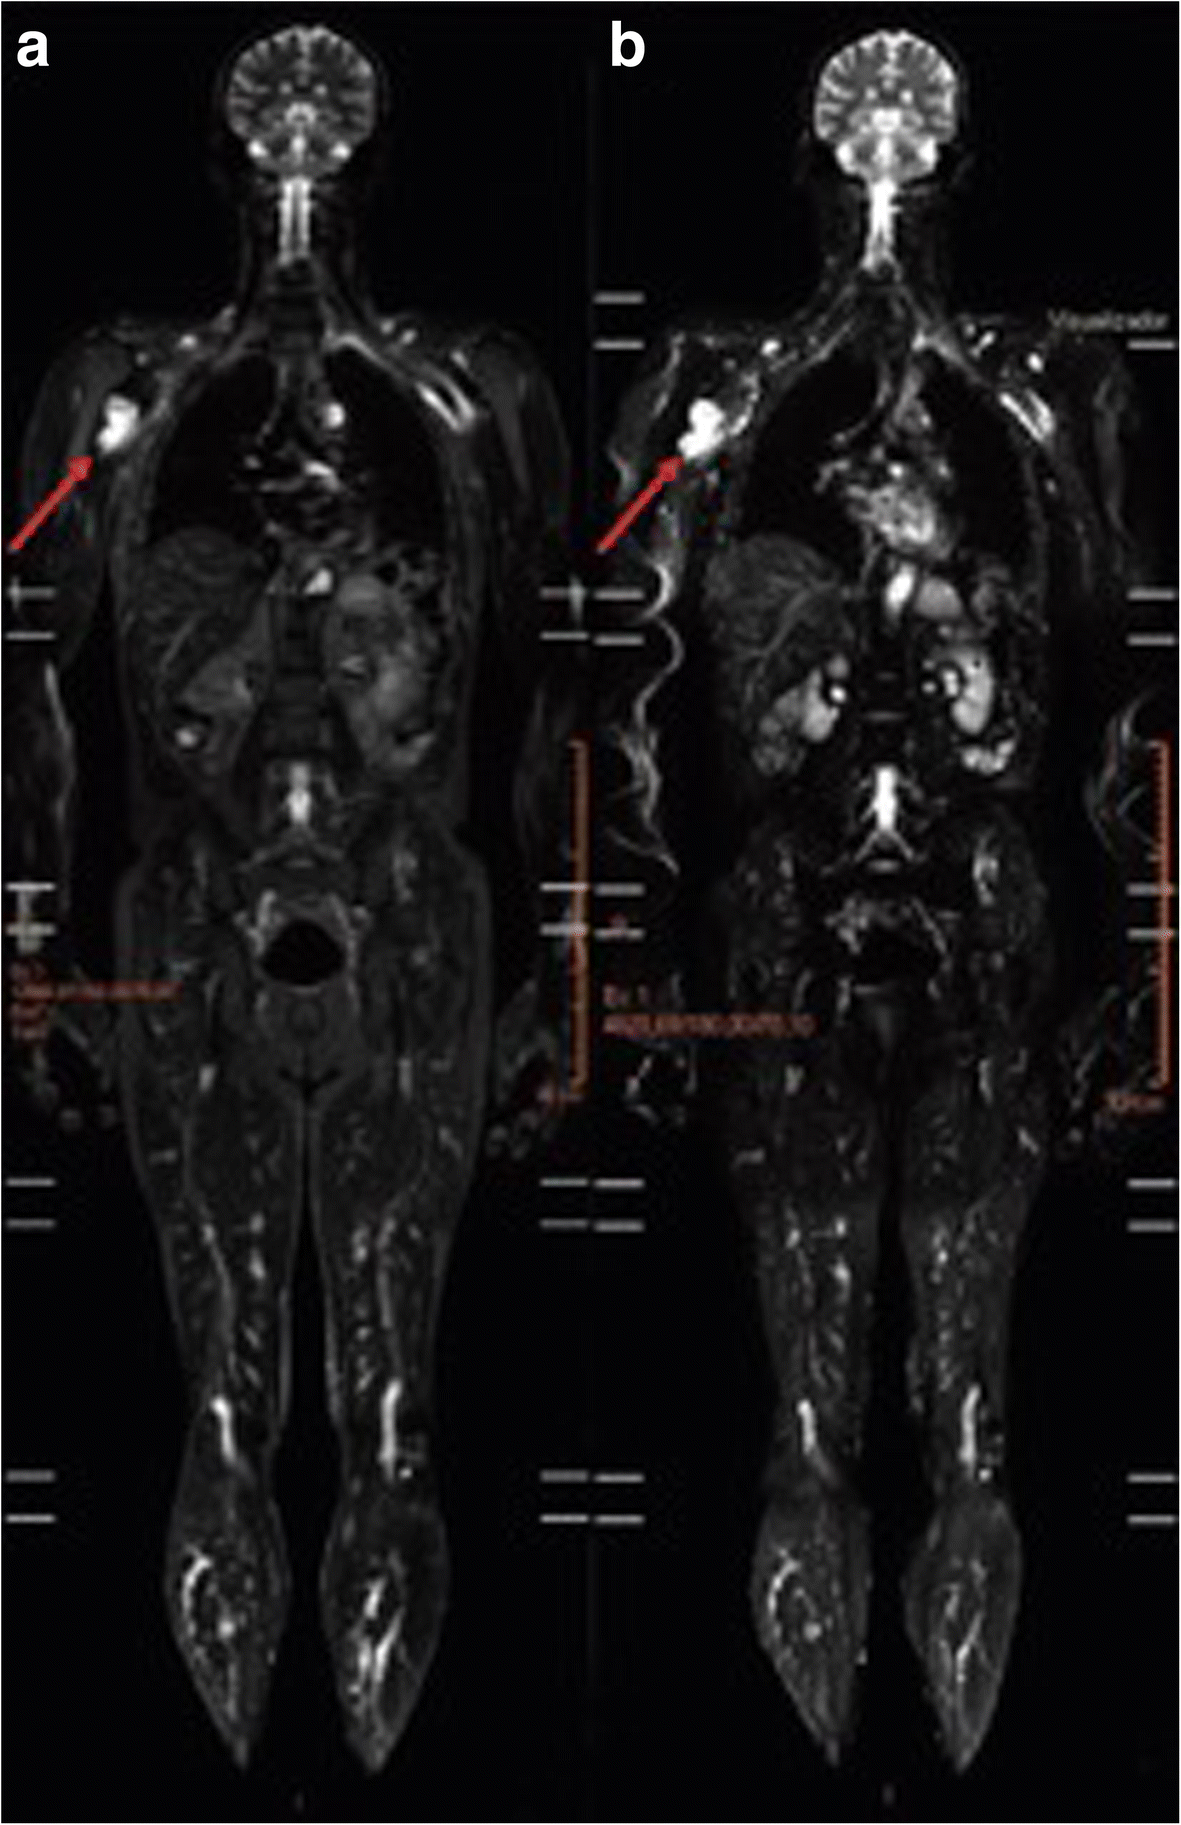

Mri scans can help medical professionals detect cancer. Wb mri uses a small number of sequences, which minimizes the slice number and enables fast coverage of the. Many cancers and other diseases do not cause symptoms until the advanced.

Whole body mri is whole body mri cancer screening screening for cancer risk adelaidemri is pleased to announce a service for patients who are known to be at high risk of developing various cancers, based on a recent 10 year study that has validated this role for whole body mri. Lung cancer patients would have been fully assessed in just 13 days, as opposed to 19 days using multiple scans. Whole body mri screening may detect small cancers allowing you to seek treatment early.

In addition, such an extended examination may be useful for systemic diseases (e.g., bechterew’s disease), when several anatomical areas are affected, or when looking for tumor metastases, when it is. A full body mri scan that you suggest would probably take, from prep time to completion, close to.2 to 3 hours. Even longer if they see something that will require them to do more precision scans.